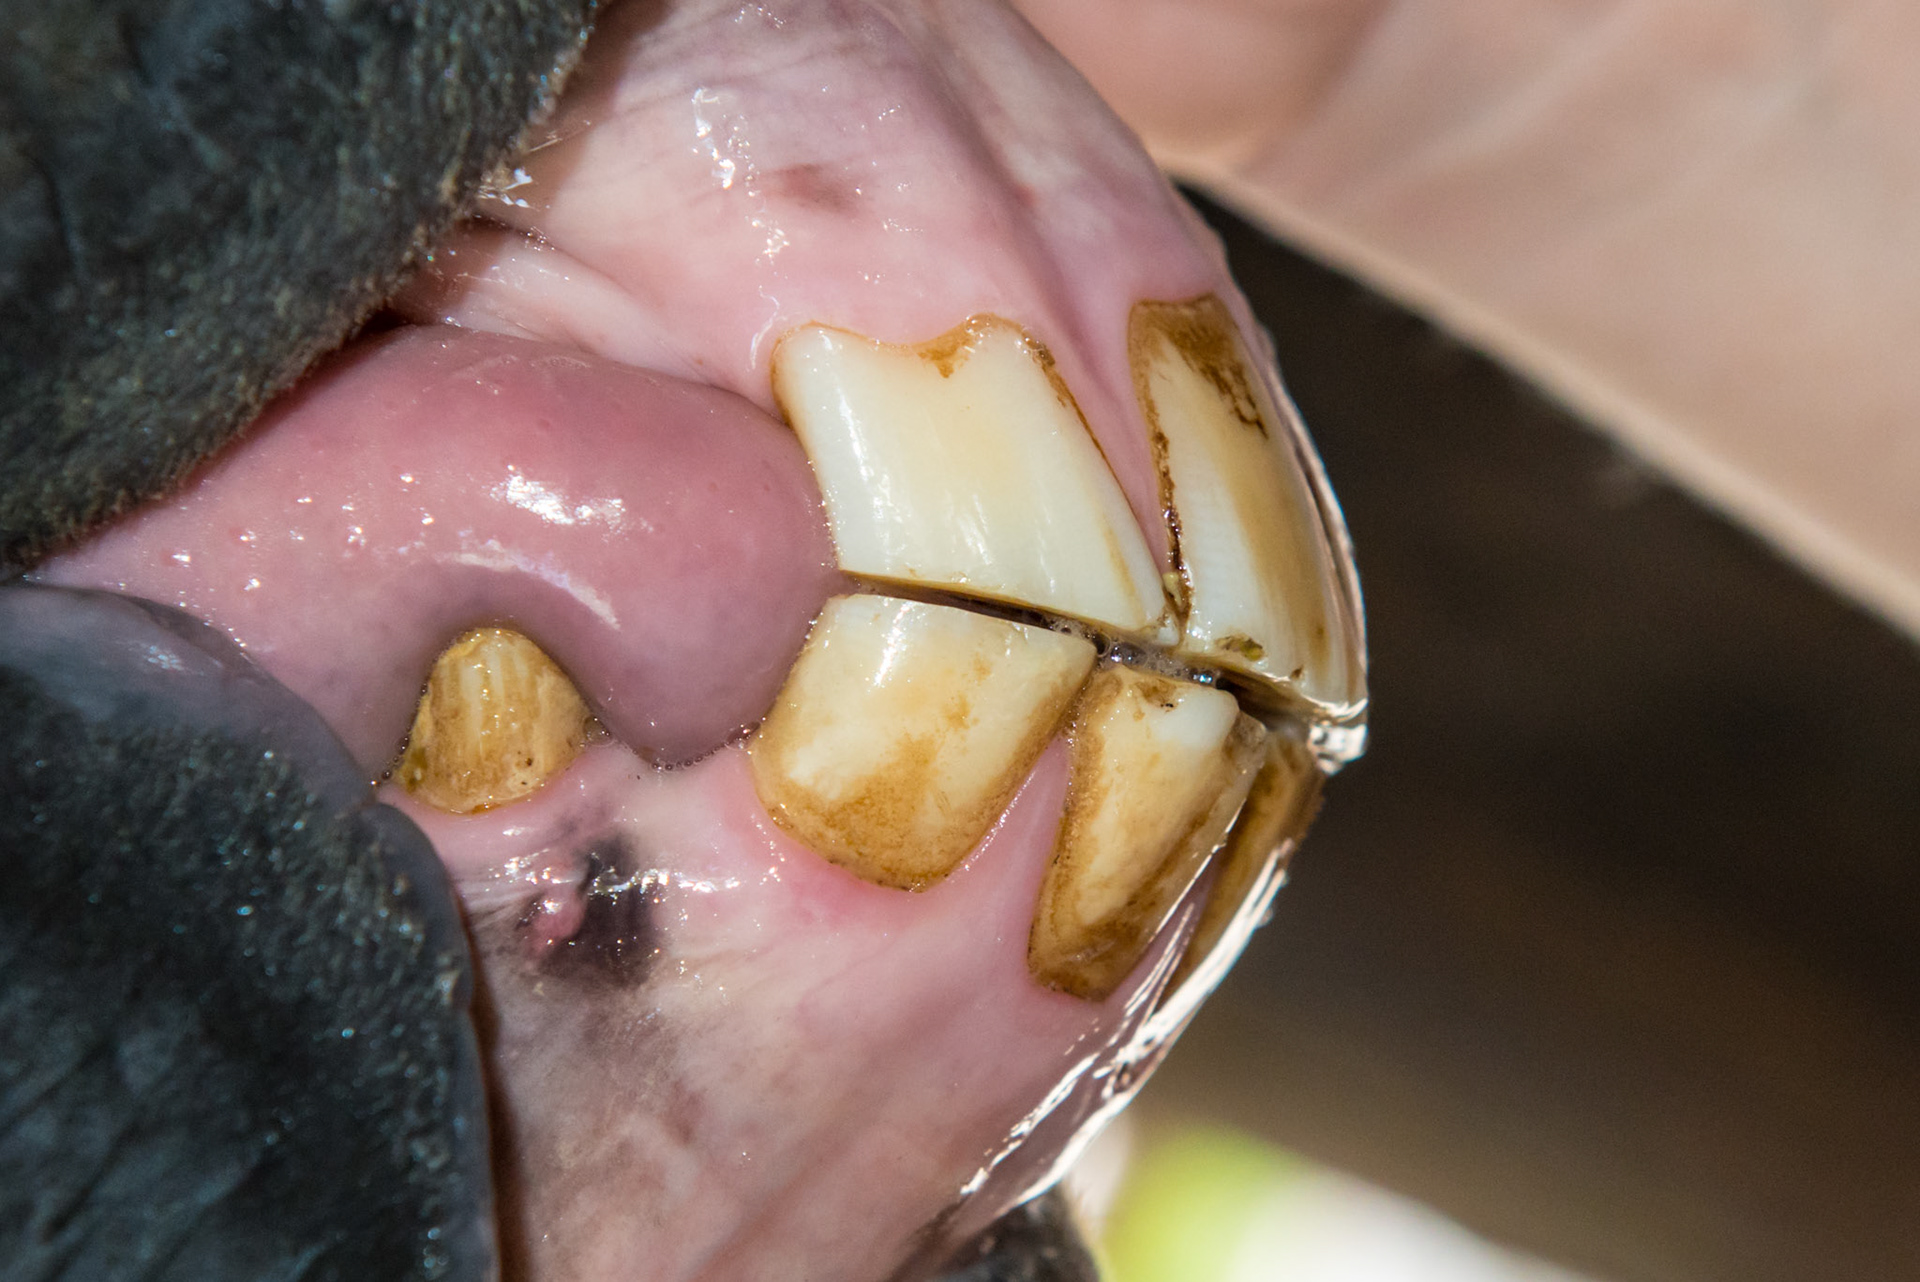

6yr 5mo Abnormally shaped #303